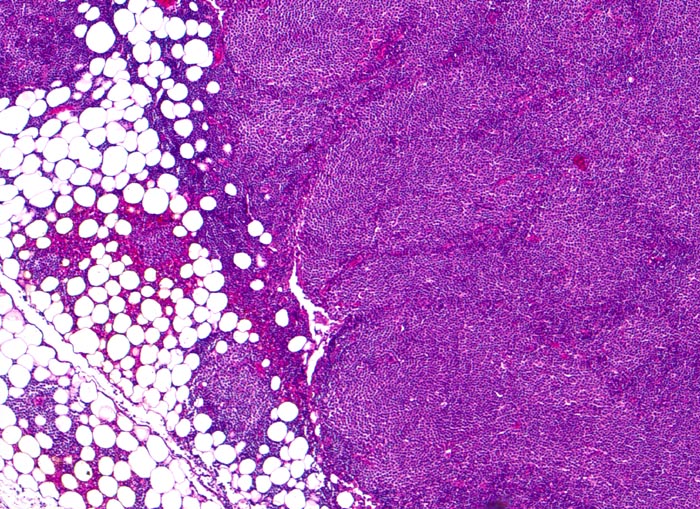

PathoPic – image database / PathoPic ID 3927 - chronische lymphozytische Leukämie vom B-Zell Typ

chronische lymphozytische Leukämie vom B-Zell Typ

Lymphknoten, inguinal

Diffuse CLL-Inifiltration des Lymphknotens mit Übergreifen des neoplastischen Infiltrates auf das umgebende Fettgewebe. Die hellen Areale entsprechen Proliferationszentren (Pseudofollikel) bestehend aus Lymphozyten, Prolymphozyten und Paraimmunoblasten.

Asymptomatische Patientin mit generalisierter Lymphknotenvergrösserung. Zufallsbefund.

Histologie

50